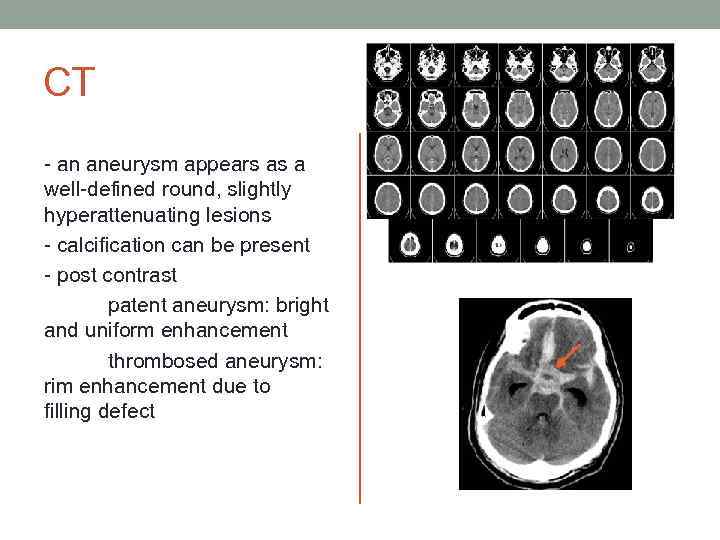

CT - an aneurysm appears as a well-defined round, slightly hyperattenuating lesions - calcification can be present - post contrast patent aneurysm: bright and uniform enhancement thrombosed aneurysm: rim enhancement due to filling defect